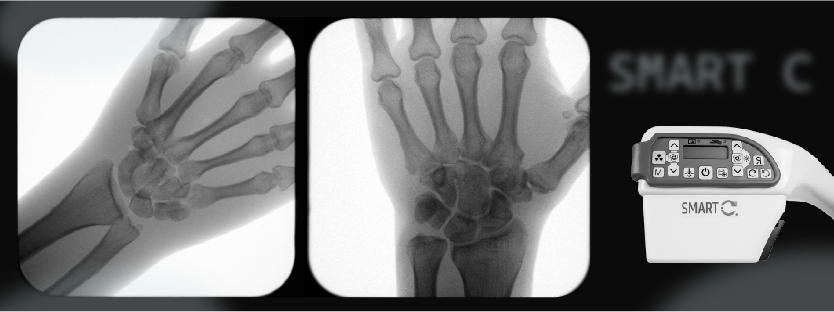

X-Ray images can be used to determine the biological age of a person by looking at the growth plates in their bones. Growth plates, also known as epiphyseal plates, are areas of developing tissue located at the ends of bones in children and teenagers. These plates are responsible for allowing bones to grow in length and are made up of hyaline cartilage, which is gradually replaced by bone as a person ages.

The width and shape of growth plates in x-ray images can provide an estimate of a person’s biological age, as these areas change over time as a person grows and develops. By measuring the width of the growth plates, medical professionals can determine the amount of growth that has taken place and, therefore, estimate the person’s age. Additionally, the shape of the growth plates can provide additional information, such as whether a person is still growing or if they have reached their full height.

By examining the growth plates in a person’s bones, medical professionals can get a clear picture of their true age, regardless of any discrepancies with their chronological age. This information can be used to monitor a person’s growth and development and make informed decisions about their care.

State of the art detector & software: SMART-C® contains a highly sensitive detector and advanced image processing algorithms that enables medical professionals to view and assess growth plate development with high quality x-ray images, in order to determine an athlete’s biological age.